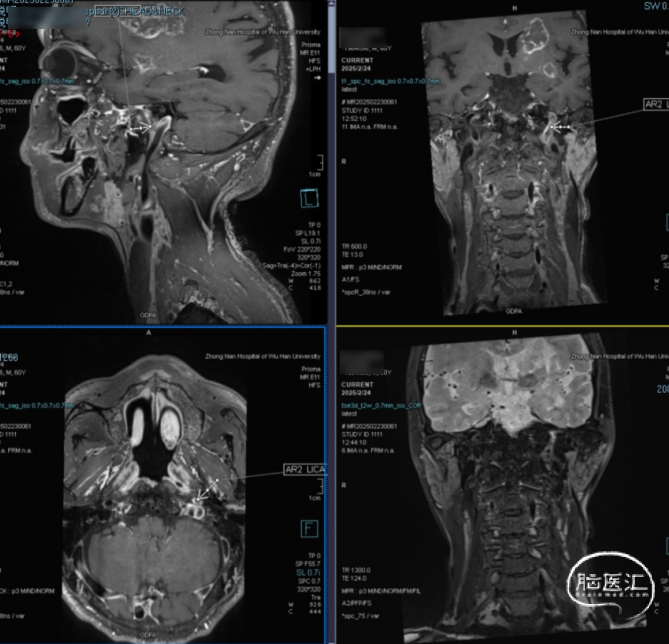

术前DSA造影显示左侧颈内动脉自起始段闭塞,C6眼段以上供血区由颈外动脉眼动脉反向代偿供血,左侧大脑中动脉供血区由前交通动脉代偿供血。

高分辨核磁:颈动脉斑块分析提示左侧颈内动脉全程管径缩窄,C1及C4-C5段不稳定斑块形成伴管腔闭塞。